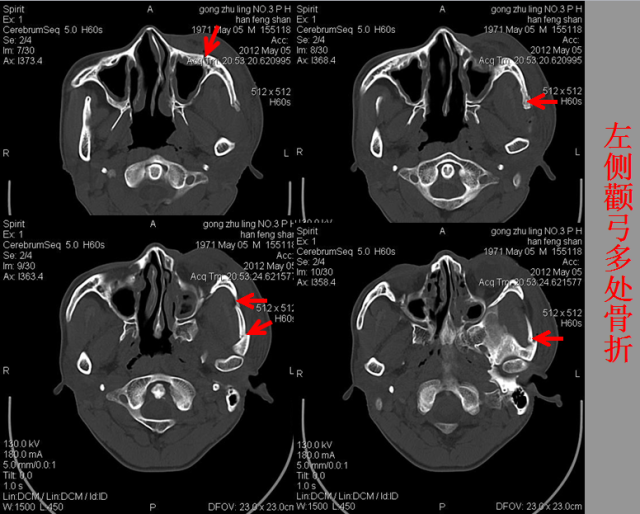

急性颅脑损伤篇

03